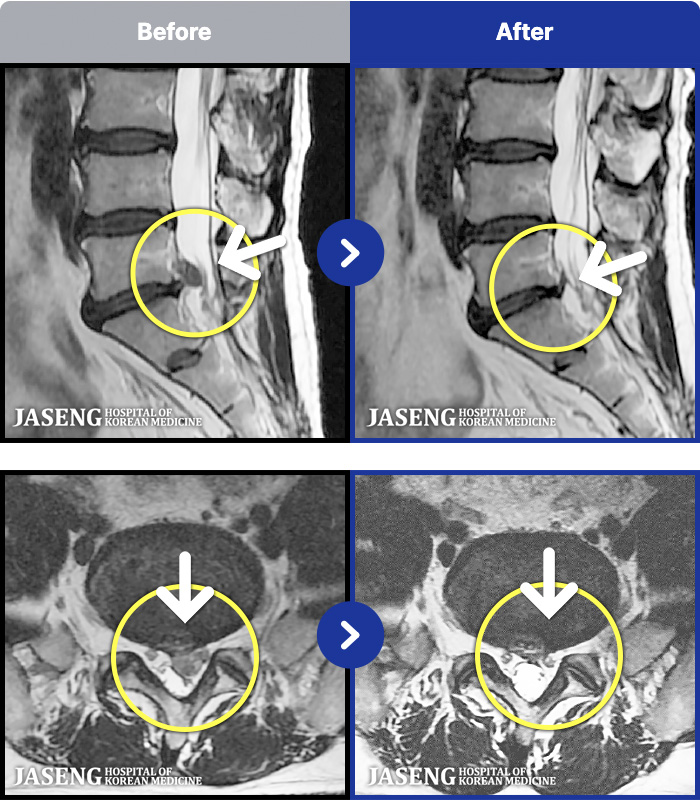

MRI ġ

1,304 MRI ũ ʸ Ȯϼ.